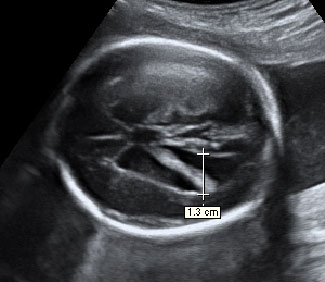

Corazón fetal en el que se aprecia una mancha brillante o foco ecogénito

La imagen de la flecha indica el foco ecogénito en el ventrículo izquierdo.

Ecografía Embarazo 2D y 3D Semana 20 - MALFORMACIONES FETALES